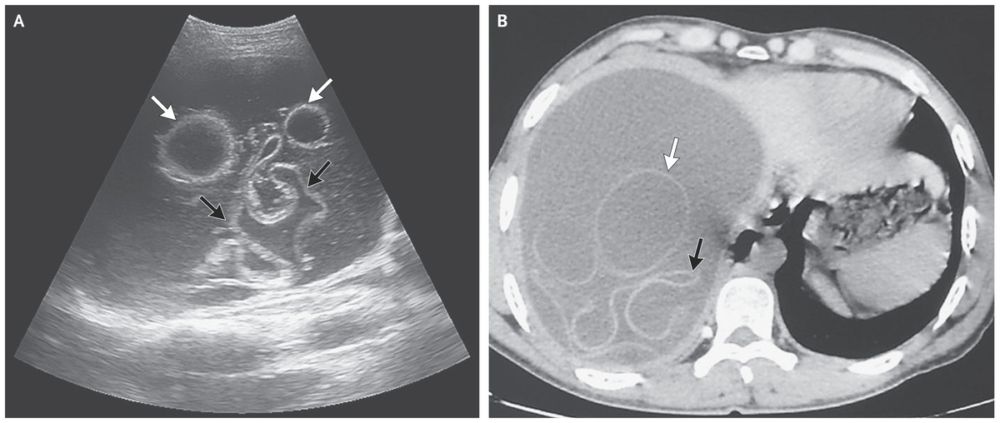

Ultrasonography (Panel A) and computed tomography (Panel B) of the abdomen revealed a large cyst in the right lobe of the liver, containing hydatid membranes (black arrows) and daughter vesicles (white arrows).